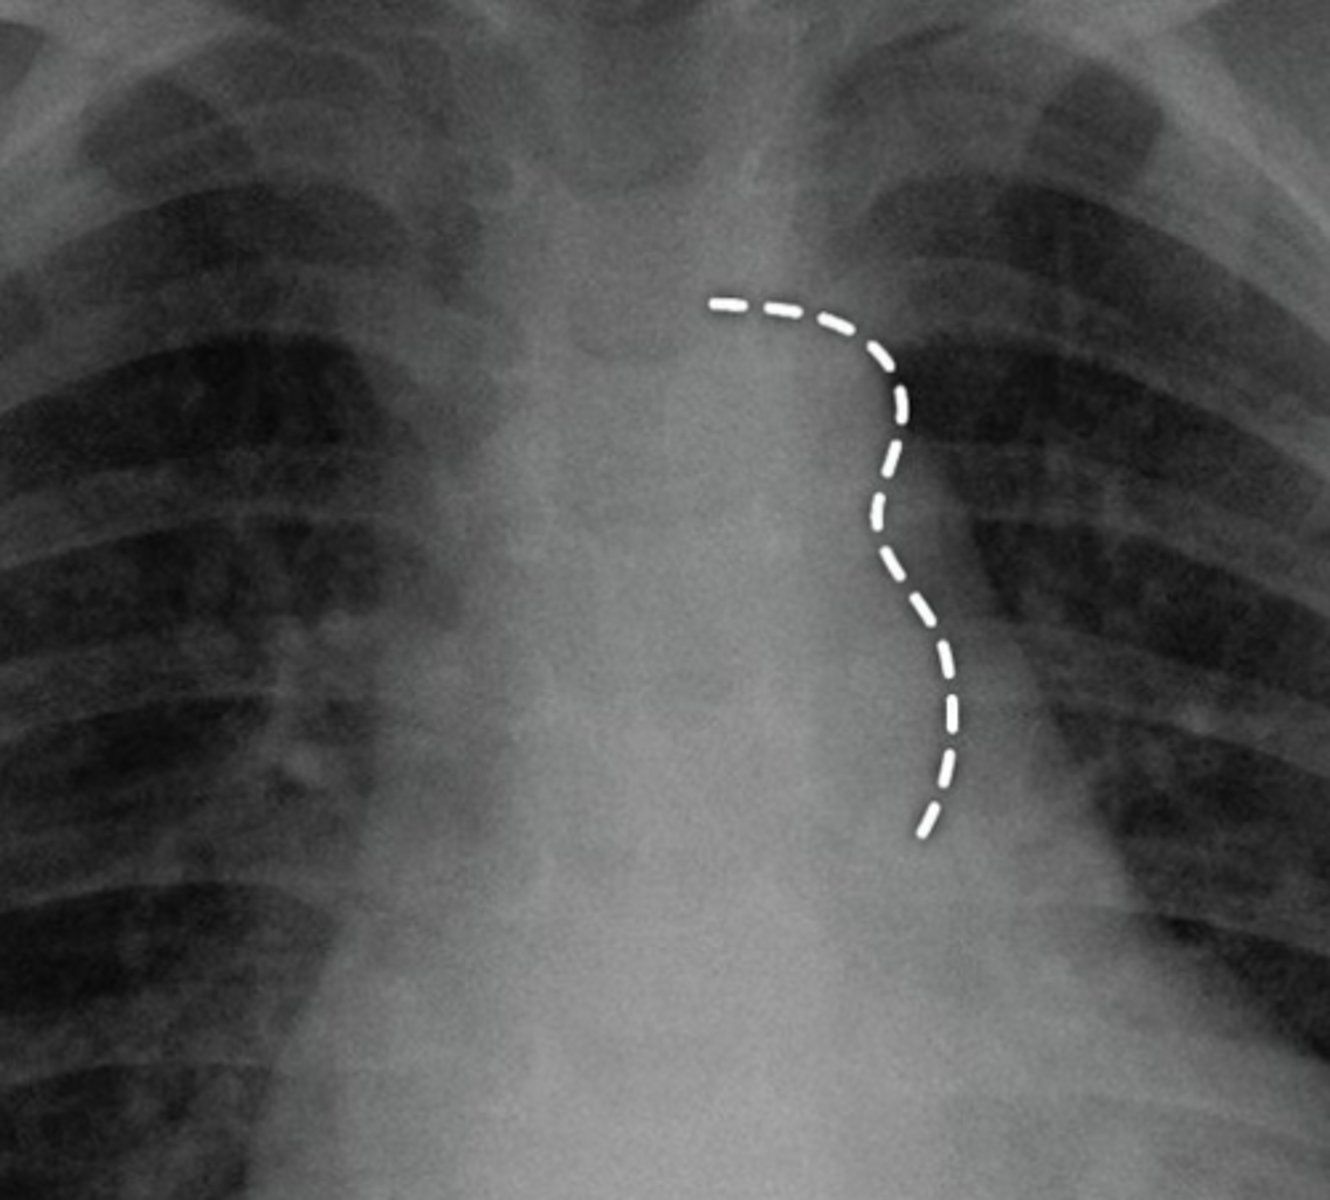

What is coarctation of the aorta?

Congenital narrowing of the aorta.

What are the key features of infantile coarctation of the aorta?

Symptomatic in early childhood, tubular hypoplasia of the aortic arch, occurs proximal to a PDA.

What are the key features of adult coarctation of the aorta?

Narrowing opposite a closed ductus arteriosus, distal to the great vessels from the aortic arch.

What is the chest radiograph finding in coarctation of the aorta?

Figure 3 sign.